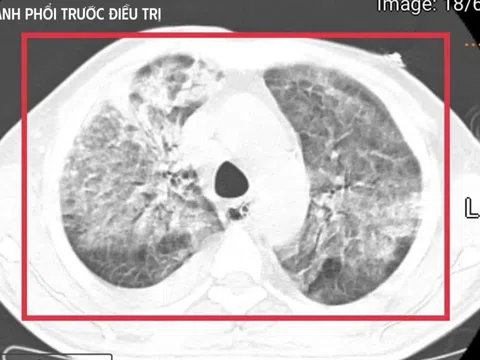

Cúm A: Cảnh báo nguy hiểm khi lạm dụng thuốc điều trị tại nhà

Cúm A là loại virus cúm thường gây ra các đợt dịch cúm mùa hàng năm và có khả năng gây đại dịch toàn...